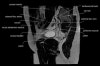

- Coronal section

T1 Allows for evaluation of both hips simultaneously even though the patient may be symptomatic in only one hip.

T2 allows for detection of abnormal fluid in both hips which may be seen in avascular necrosis, stress fractures, muscle tears or perilabral cysts.